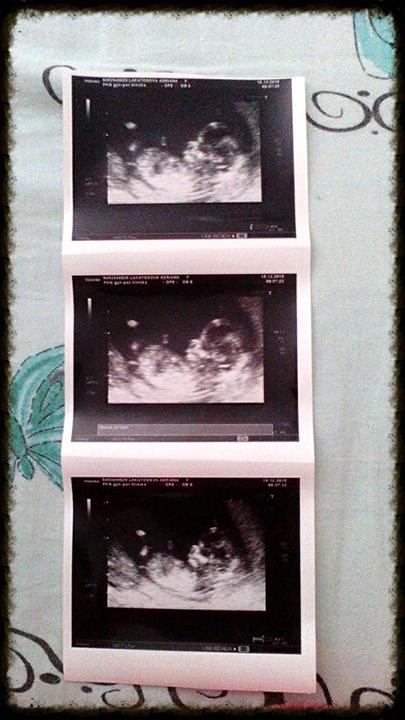

Tak první screening máme za sebou ..miláček žádné vady nemá ..je z cela v pořádku jinak zítra začínáme konečně 13 týden :3